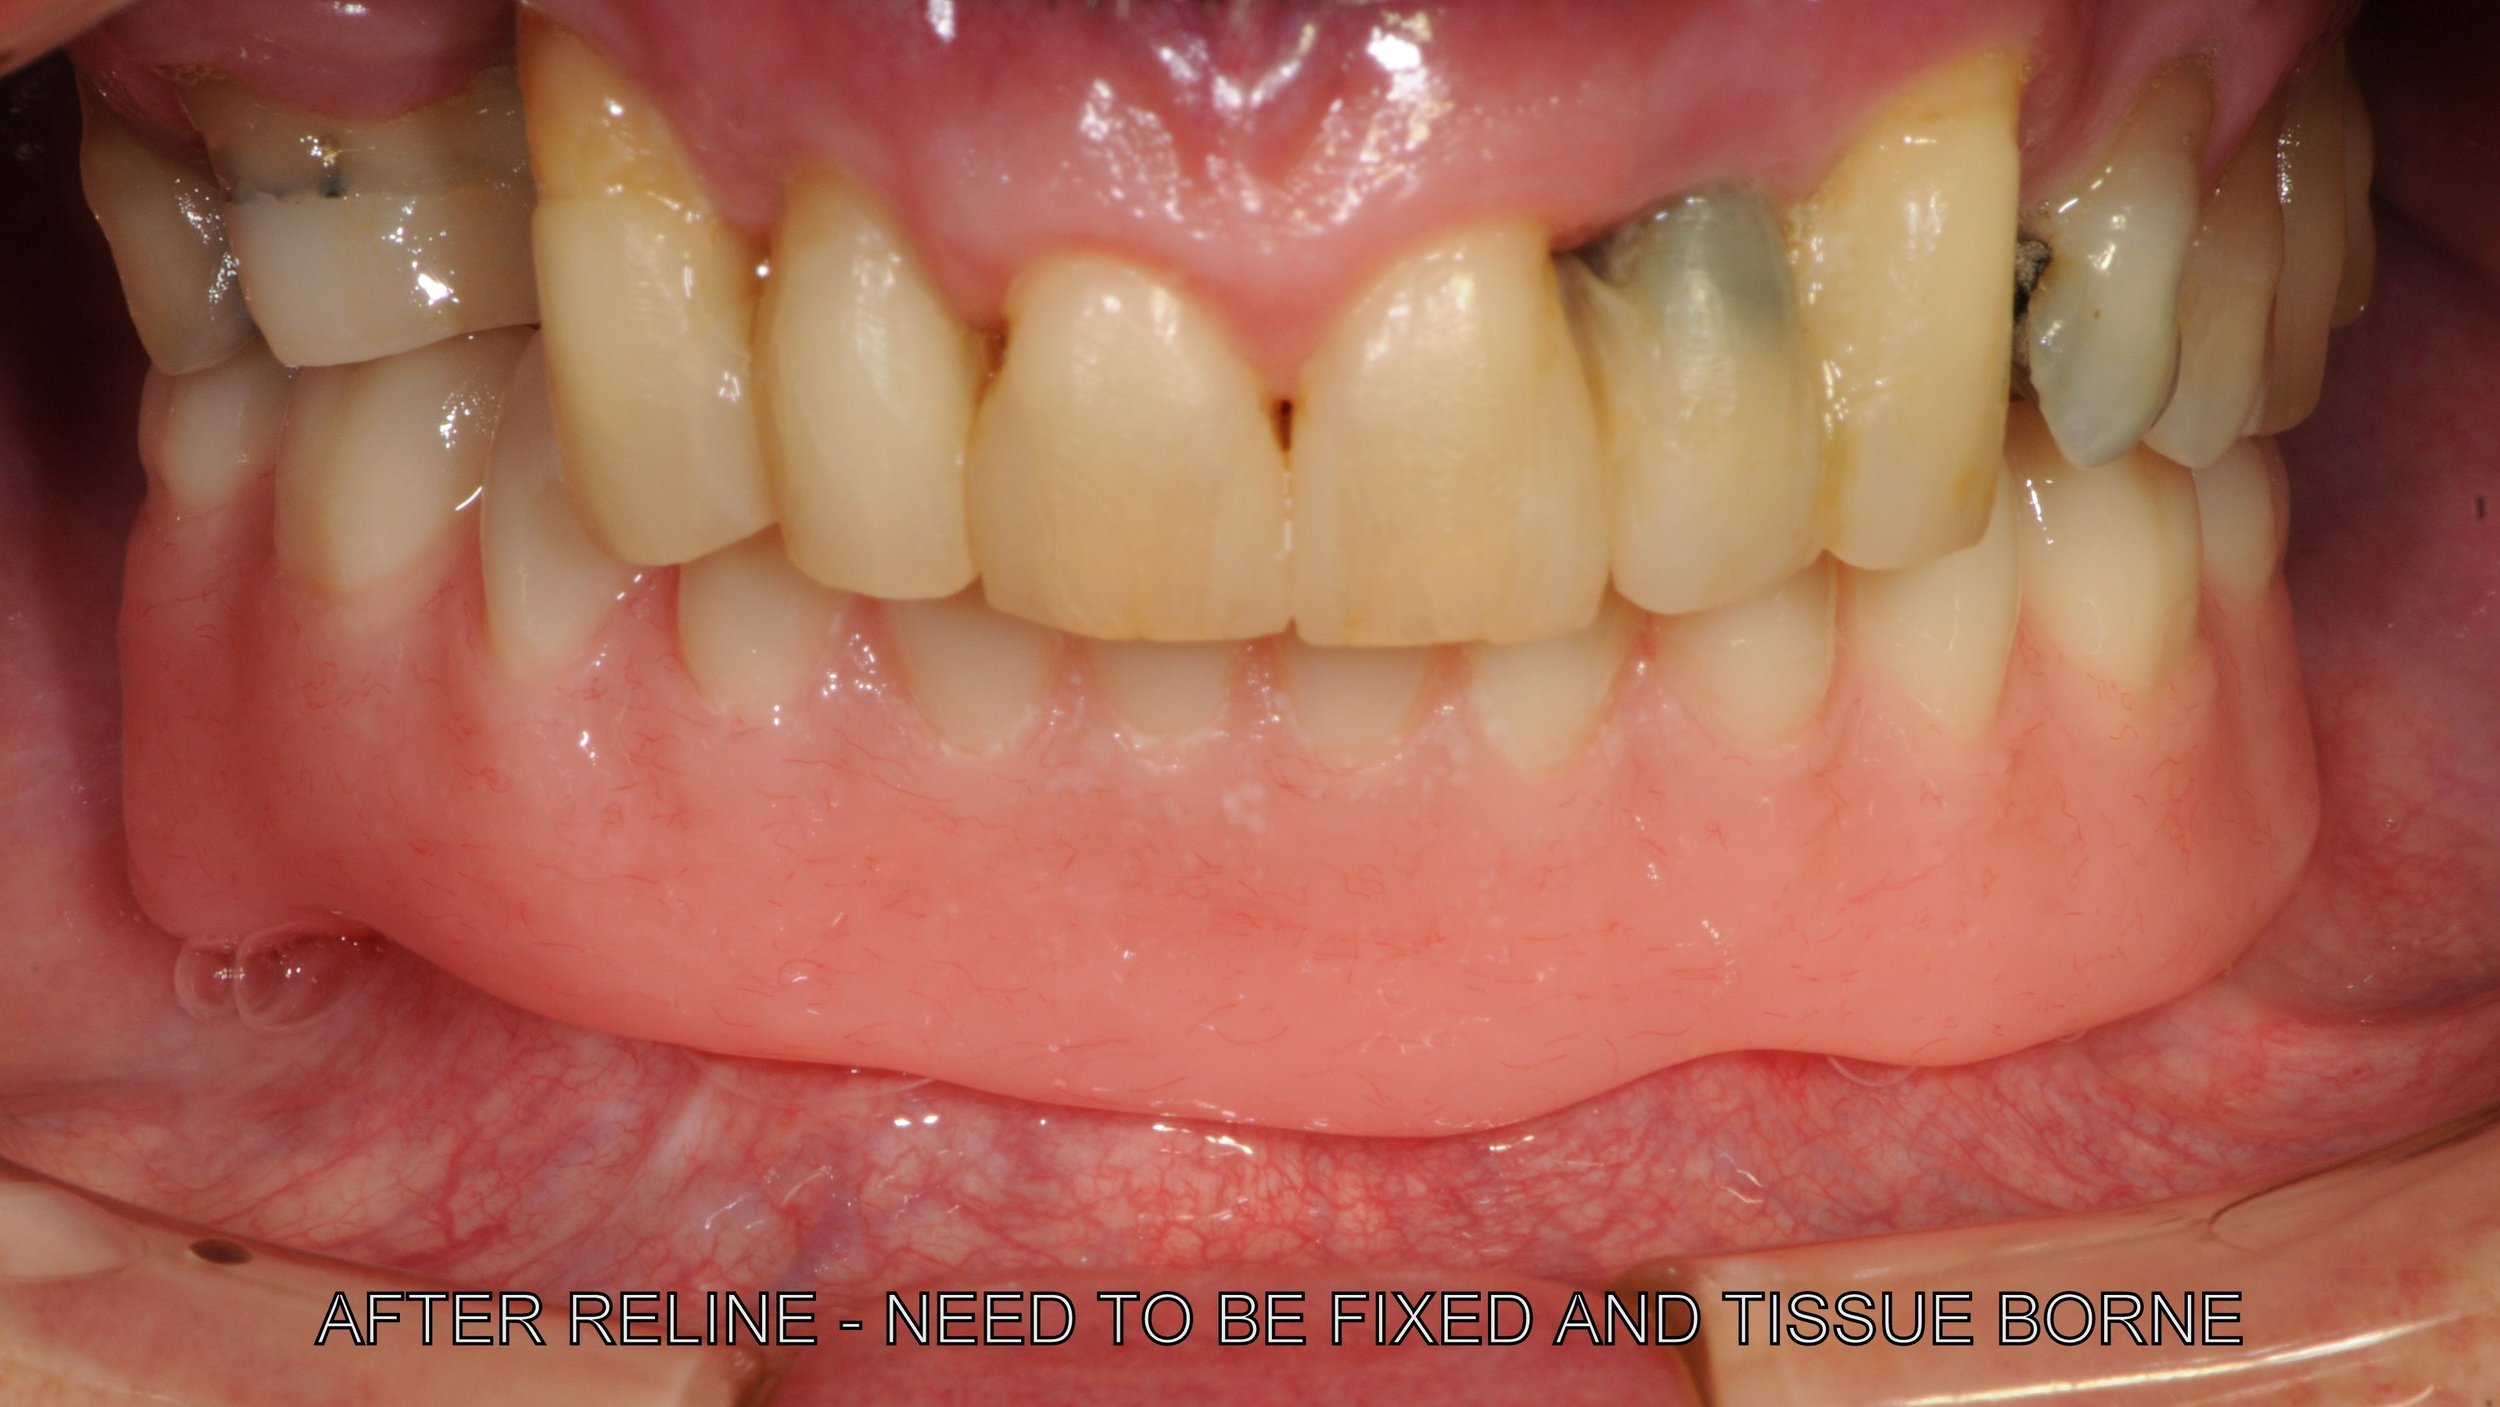

The remaining lower 6 front teeth that were deemed to have insufficient bone for longevity and unsuitable for a bite reconstruction, these teeth were extracted.

-

An OPG radiograph after the 6 extractions and Dr. Darveniza in 2014 surgically placed 2 Branemark implant fixtures between the existing 2 Ankylosis implant fixtures along with some artificial powdered RTR bone. Bone grafting adjacent to these Ankylosis implants was required following the extraction of the lower canines which had bone loss adjacent the 34 and 44 implant fixtures.